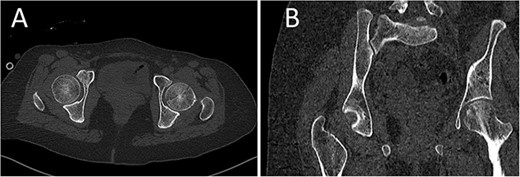

A medically free 42-year female presented to our institute as a life-saving case from a different hospital as she was a victim of unrestrained road traffic accident 2 days prior to presentation. Upon assessment in the emergency department (ER), she was conscious and oriented, and was found to have bilateral lung contusion, and multiple fractures of ribs. She also had a left sided vertical femoral head fracture dislocation comprising around 40% of the femoral head (Fig. 1). Closed reduction under conscious sedation was done in the ER, which was successful based on post-reduction imaging studies (Fig. 2). Her chest injuries were treated with chest tube and observation for 10 days. During that time, discussion was made with the patient regarding her situation and conservative management was chosen by way of bed rest and continuation of skeletal traction for 4 weeks with serial radiographs in the hospital on a weekly basis after clearance of her chest injuries. Skeletal traction was discontinued and she was advised to continue bed to wheelchair mobilization for an additional 2 weeks. After 6-weeks from the injury, a Computed Tomography (CT) was done to the patient and revealed signs of fracture healing (Fig. 3). At 3-years after the injury, she was found to have full painless range of motion of the affected hip and has resumed her activity of daily living without any complaints and the images showed a symmetrical joint space of the hips (Fig. 4).

Prereduction anteroposterior (AP) radiographs of the pelvis showing a left side fracture dislocation of the left proximal femur (A) and postreduction radiographs of the left hip (B) showing a concentric hip joint.